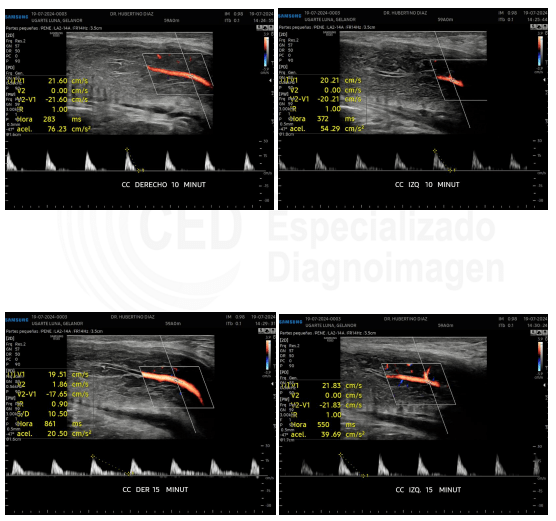

Ecografía doppler del mismo paciente con enfermedad de La Peyronie e inicios de disfunción eréctil

En el infome de la ecografía doppler se aprecian valores arteriales de pico sistólico máximo menores a 30 cm/s, lo que implica una insuficiencia arterial o de llenado. Así mismo los picos diastólicos permanenec menores a 5 cm%s, lo que indica que NO hay afectación venosa, cononcida como fuga venosa.